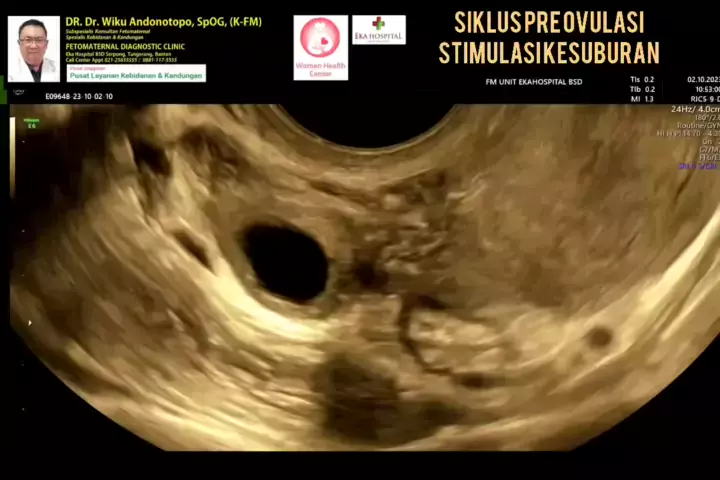

Stimulasi kesuburan (Pre Ovulasi) pasien infertilitas.... #drwikuandonotopo #drwiku_andonotopo #polikandunganekahospitalbsd #fetomaternalekahospitalbsd #usgfetomaternalekahospitalbsd #konsultanfetomaternalekahospitalbsd #ekahospitalbsd #ekahospitalcibubur #ekahospitalbekasi #ekahospitalpekanbaru #fetomaternalbekasi #fetomaternalcibubur #fetomaternal #konsultanfetomaternal #usg #usg4d #perkembanganbayi #perkembanganjanin # #melahirkannyaman #melahirkannormal #melahirkancesar #janin #lahiran #...